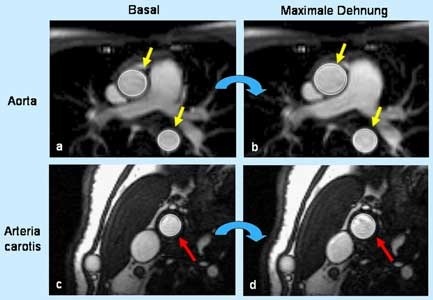

An der Studie nahmen 22 junge Leute teil, und zwar Nichtraucher und Raucher im Alter um die 30 Jahre. Mit Hilfe der Magnetresonanz-Bildgebung wurde bei ihnen vor allem die Elastizität von Arterienabschnitten in der Ellbeuge, der Aorta und der Halsschlagader untersucht. "An all diesen Orten waren bei den Rauchern deutliche Funktionsstörungen nachweisbar", so Wiesmann.

Die Arbeit entstand in einer wissenschaftlichen Kooperation zwischen der Medizinischen Klinik der Uni Würzburg und der Universität Oxford. Hierbei wurde erstmals nachgewiesen, dass der Zigarettenkonsum bei jungen, gesunden Menschen nicht nur eine Funktionsstörung des peripheren Kreislaufsystems, sondern auch sehr zentraler Arterien mit sich bringt. Wiesmann erhielt dafür einen von drei Preisen für Nachwuchsforscher, die von der International Society of Cardiovascular Magnetic Resonance vergeben werden. Seine Auszeichnung ist mit 750 Euro dotiert.

Die Magnetresonanz-Technik könnte zukünftig klinisch eine wichtige Rolle für die Abschätzung des Schlaganfall- oder Herzinfarktrisikos spielen. Im Bereich der Herz-Kreislauf-Forschung gibt sie interessante Einblicke in die Effekte neuer therapeutischer Ansätze gegen Arteriosklerose. Die Technik liefert exakte Bilder aus dem Inneren des Körpers, ohne dass hierfür ein Eingriff in den Organismus nötig ist. Sie arbeitet mit Magnetfeldern und kommt ohne Kontrastmittel und Röntgenstrahlen aus.